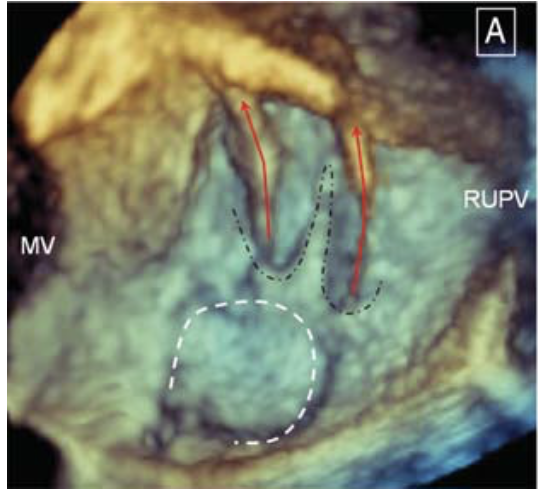

由于卵圆孔形态远比我们想象的复杂,因此在进行卵圆孔未闭介入治疗时应充分评价卵圆孔的解剖及毗邻关系,目前食道超声对卵圆孔未闭形态的全面评估非常重要。有人提出了简单和复杂的PFO(5):(1)简单PFO:解剖标准,没有复杂卵圆孔的解剖表现。(2)复杂PFO:长隧道(≥8mm)(图1);左房侧多开口(图2);合并房间隔膨出瘤(图3);复合畸形(合并小房缺等)(图4);继发隔增厚(≥10mm)或合并房间隔脂肪瘤(图5);Eustachian嵴;合并明显Eustachian瓣和Chiari网(图6)。

图2 左房面多开口(European Journal of Echocardiography (2010) 11, i19–i25)